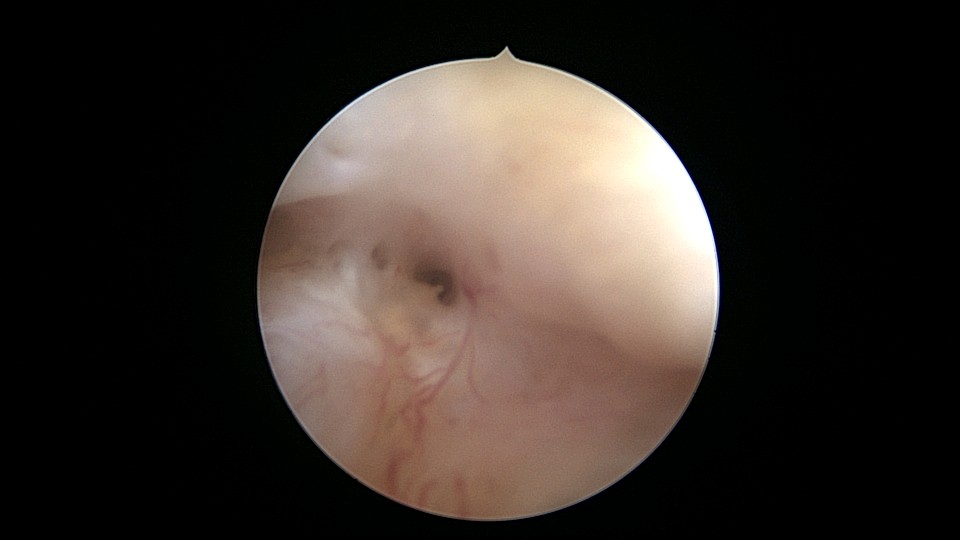

患者55岁,G5P1,顺产1次。安环20年,绝经8年。子宫后位,外阴、阴道及宫颈萎缩,宫深6.5cm,宫颈内口封闭粘连,镜鞘推开粘连,见灰白色脓液,O型环位置正常,异物钳顺利取出节育环,膨宫液冲洗脓液,宫腔无其他异常。